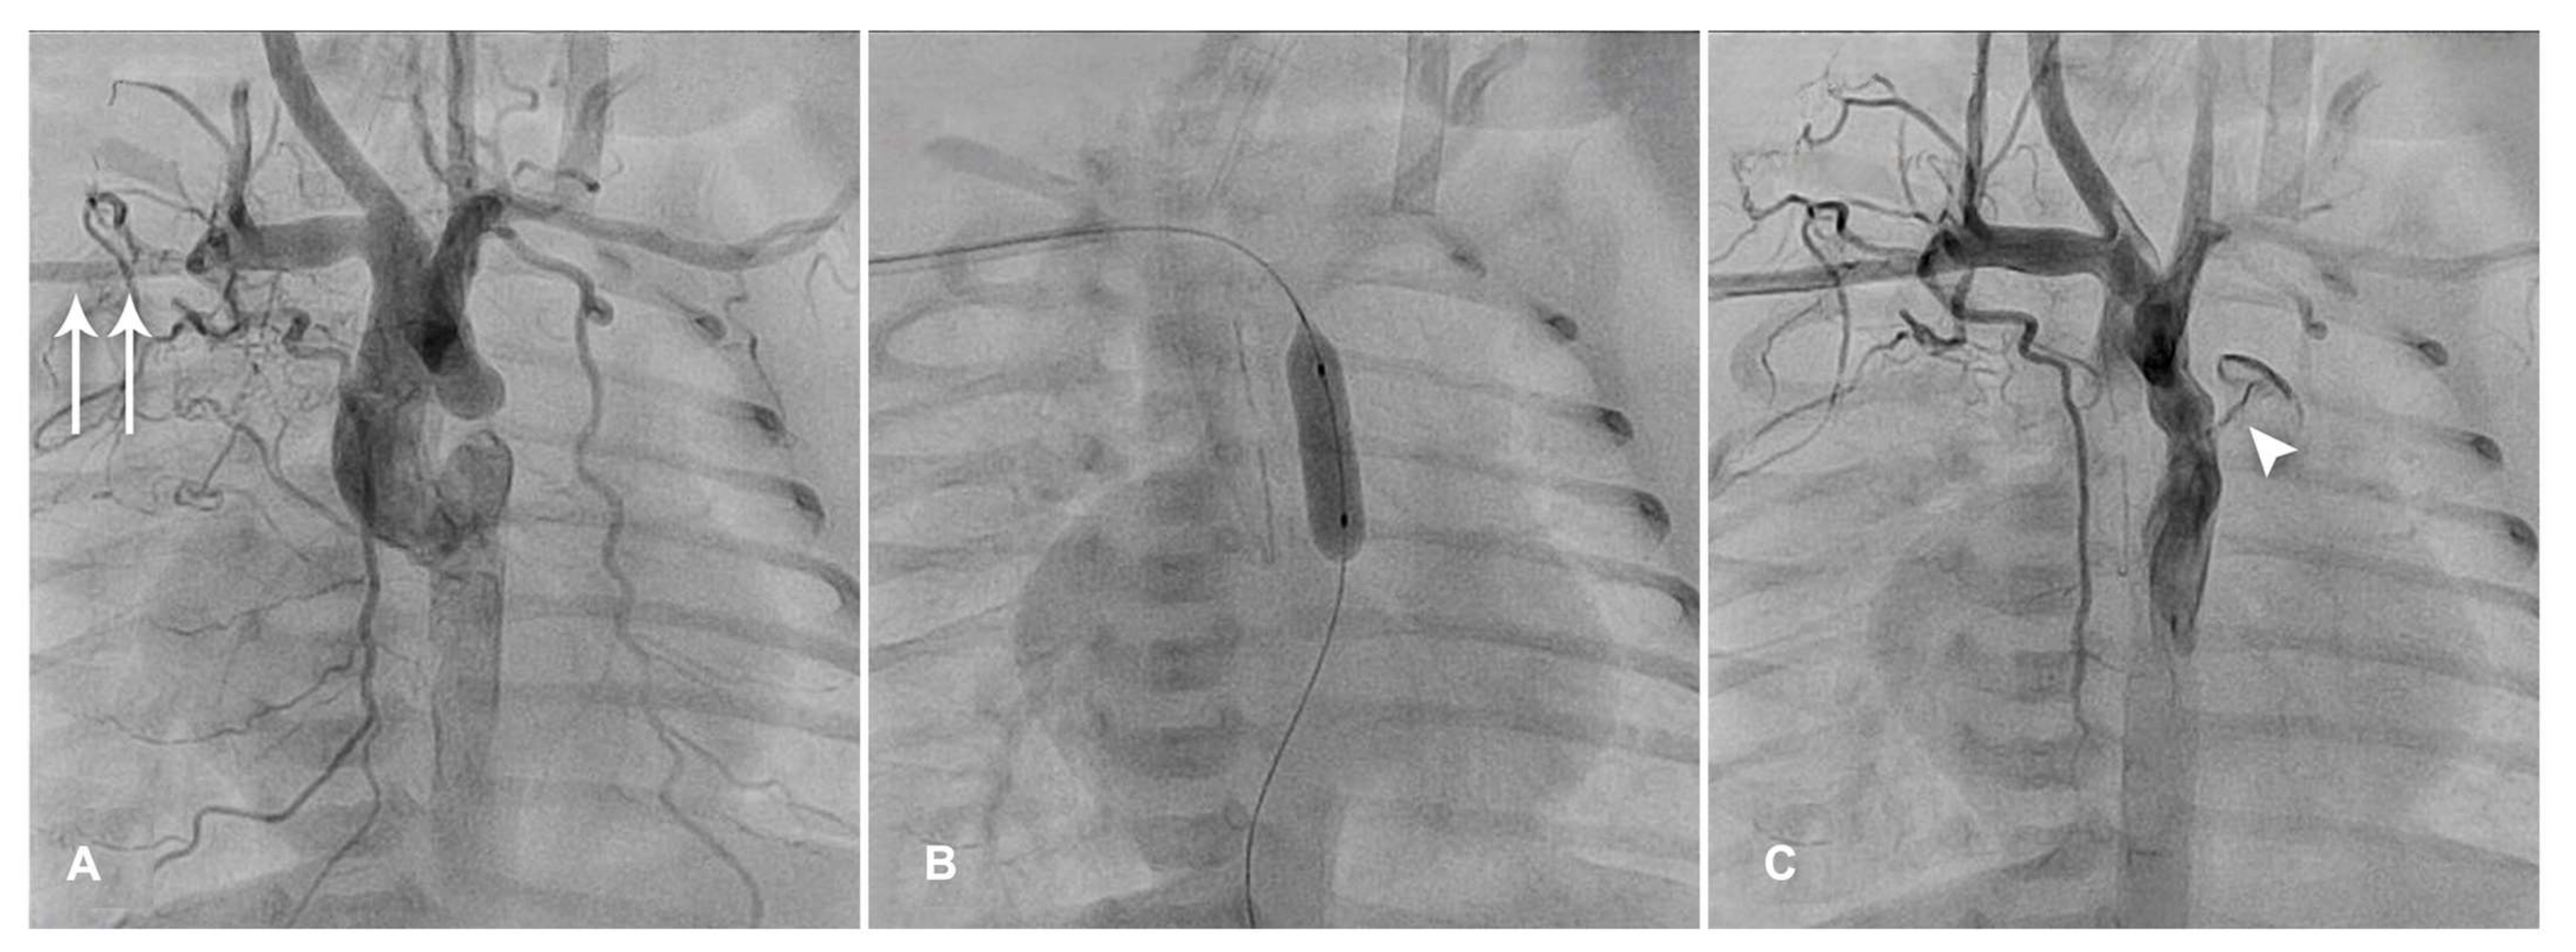

| RVOT stenting | Severe RVOT obstruction in ToF and DORV with ToF physiology with diminutive/hypoplastic PAs and surgical risk factors: prematurity, low BW, age <3 months, extracardiac condition requiring surgery | Stent migration, in-stent stenosis, stent fracture, obstruction due to somatic growth. |